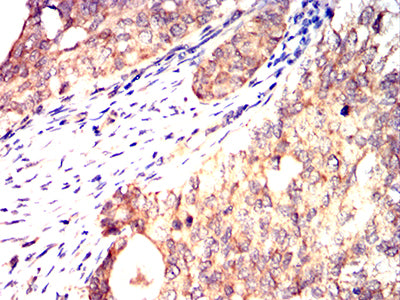

- Immunohistochemical analysis of paraffin-embedded human cervical cancer tissues using C9orf72 mouse mAb with DAB staining.